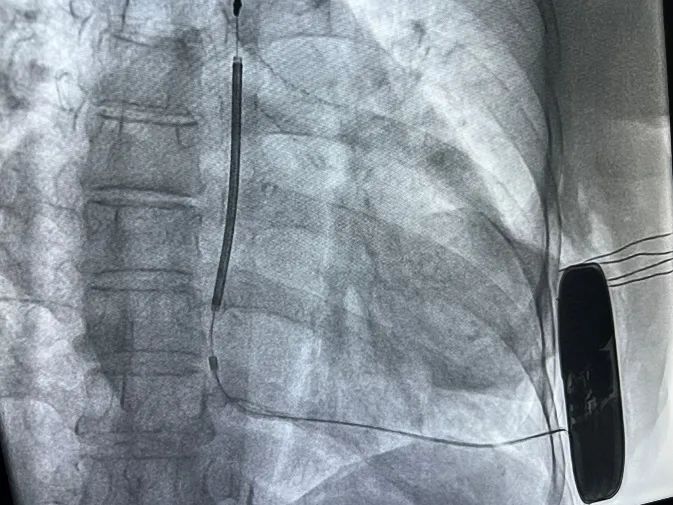

由心外科、介入室、麻醉科协作,手术在基础麻醉(镇痛)下进行,于患者左侧第5肋间沿腋中线走形切开皮肤6cm至7cm,逐层分离至皮下,分离囊袋至背阔肌与前锯肌之间。再次于剑突左上缘1cm为预定点,切开皮肤3cm,逐层分离皮下组织至筋膜层,并预埋两根缝合线,通过皮下隧道器将电极从横切口导引至囊袋,在横切口处固定电极;接着用隧道器导引除颤电极于深筋膜层至胸骨上窝位置,对所有伤口区进行有效止血,同时通过按压将隧道内空气排出,防治导线的感知受到影响。随后连接除颤装置,置入囊袋内,逐层缝合皮下组织及皮肤,术区纱布覆盖,包扎,弹力绷带加压包扎止血。

由于患者房颤,且基础情况较差,经专家讨论后决定不予术中诱颤,术后PRETORIAN评分小于30分,DFT成功率极高。